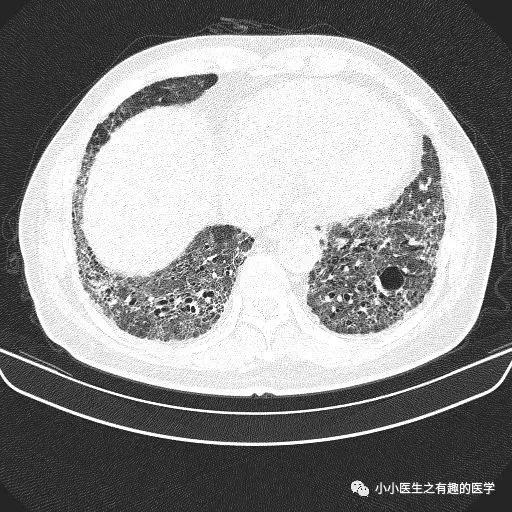

经典的间质性肺炎,就是一张网!

1.胸膜下2.网格状很多间质性肺炎,都有这个特征,是间质性肺炎的入门知识,也是很重要的知识。

假如一个患者结缔组织病,双肺多发病变,但是,胸膜下没有病灶,首先不考虑间质性肺炎,要考虑其他疾病。